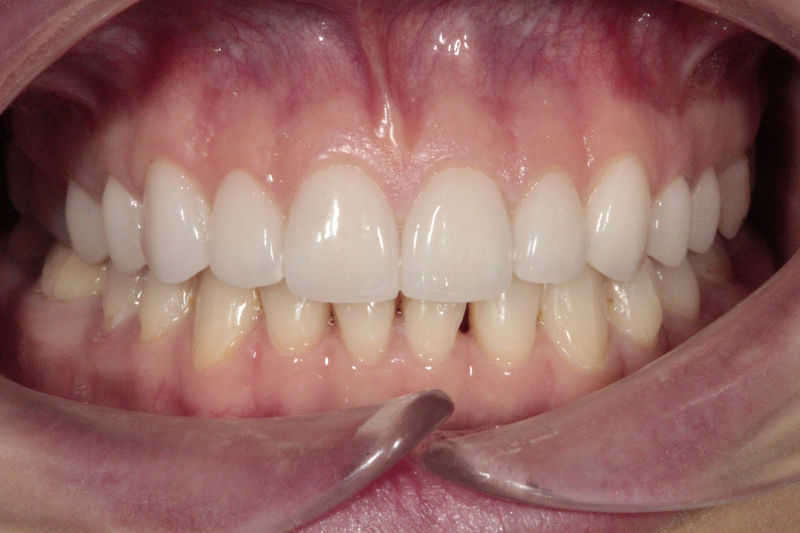

Ortodoncia y coronas.